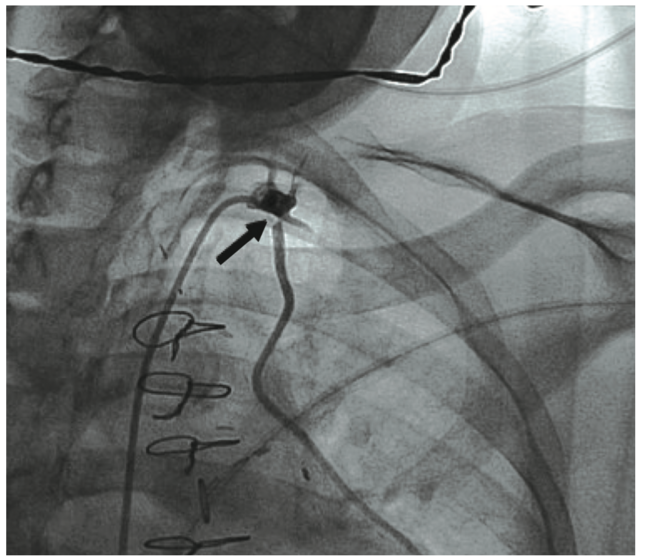

Recanalization of Acute Left Internal Mammary Artery Graft Failure by …